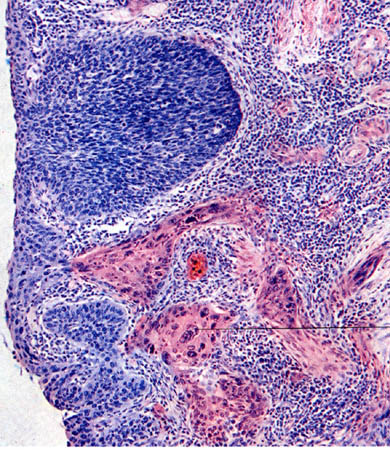

Залежно від ступеня диференціації розрізняють експансивну, апозиційну та інфільтративну (інвазивну) форми росту пухлин. Перша форма притаманна доброякісним пухлинам, друга і третя - злоякісним.

Апозиційний ріст - проміжний між експансивним та інфільтративним. Пухлина росте із множинних точок росту - вогнищевих проліфератів, які складають “пухлинне поле”. Пухлинна трансформація (малігнізація) здійснюється послідовно з центра до периферії і завершується злиттям вогнищ малігнізації у єдиний вузол.

Інфільтративний ріст характеризується тим, що пухлинні елементи поширюються у напрямках найменшого опору і вростають у навколишні тканини, руйнуючи їх. Межі пухлини в такому випадку не чіткі, стерті.